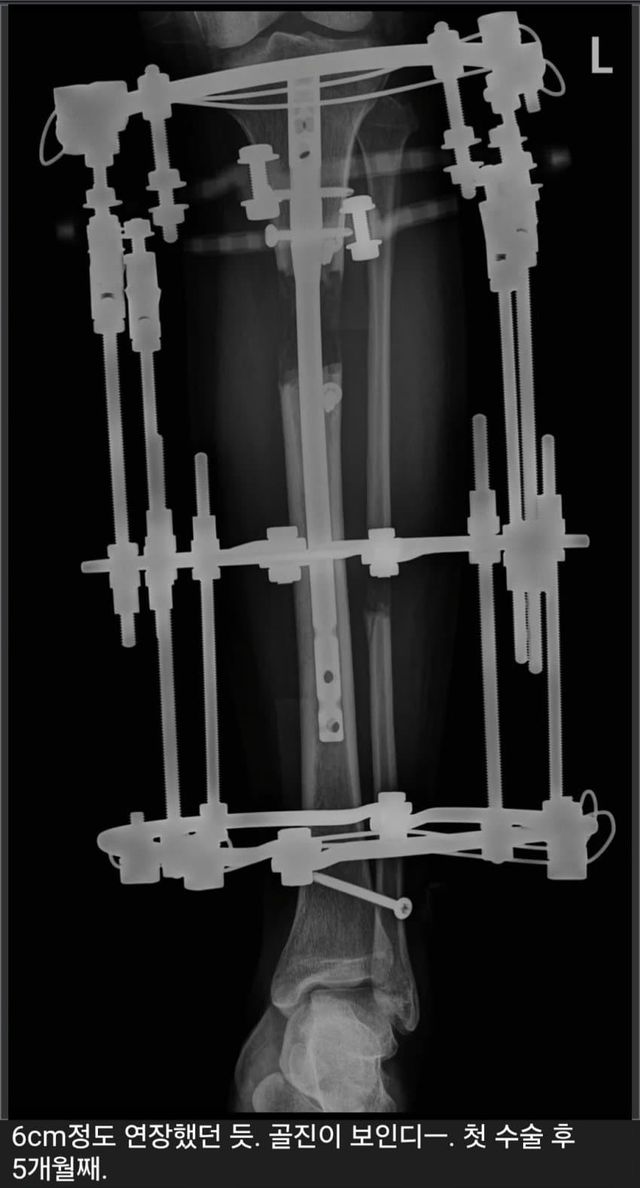

1. 6cm 늘림

2. 다리 아픔

3. 3.5cm 줄임